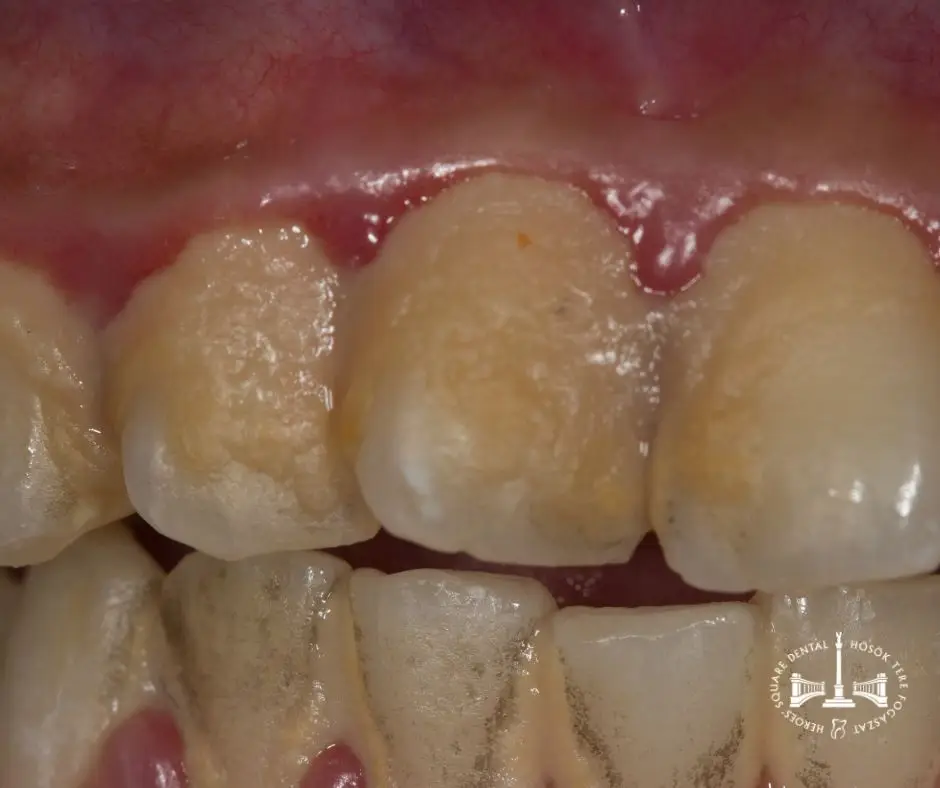

plakk, fogkő, gyulladt íny

• Az íny duzzadása és vörös, fénylő megjelenése

• Rendszeres ínyvérzés fogmosás vagy étkezés közben

• Az íny puha tapintású, szivacsos állagú lesz

1. Gingivitis (kezdeti ínygyulladás): Ez a visszafordítható stádium, amikor csak az íny lágy szövete gyulladt, de a csont még nem károsodott. Az íny vörös, duzzadt, könnyen vérezhet, de még nincs tasakképződés. Megfelelő szájhigiénia és professzionális fogkő-eltávolítás általában teljesen megszünteti a problémát.

2. Enyhe parodontitis: Ebben a szakaszban már tasakok kezdenek kialakulni (3-4 mm mélység), és a fogat tartó csont enyhén károsodik. Az íny visszahúzódhat, fokozott ínyvérzés és rossz lehelet jelentkezik. Professzionális, esetleg mélyebb tisztítás szükséges.